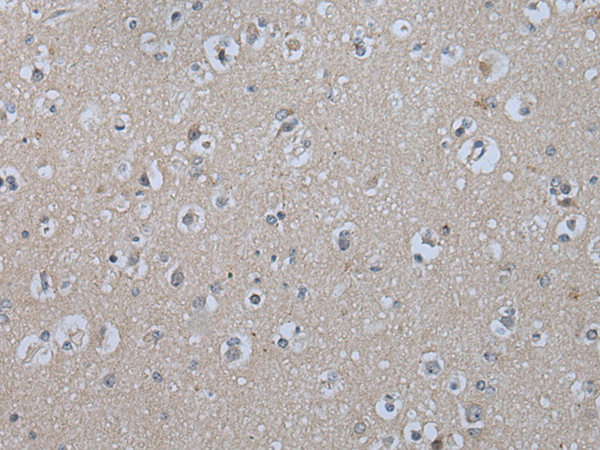

分类: 科研抗体货号: P12760别名: HHF5; CD220应用: IHC反应种属: Human, Mouse, Rat